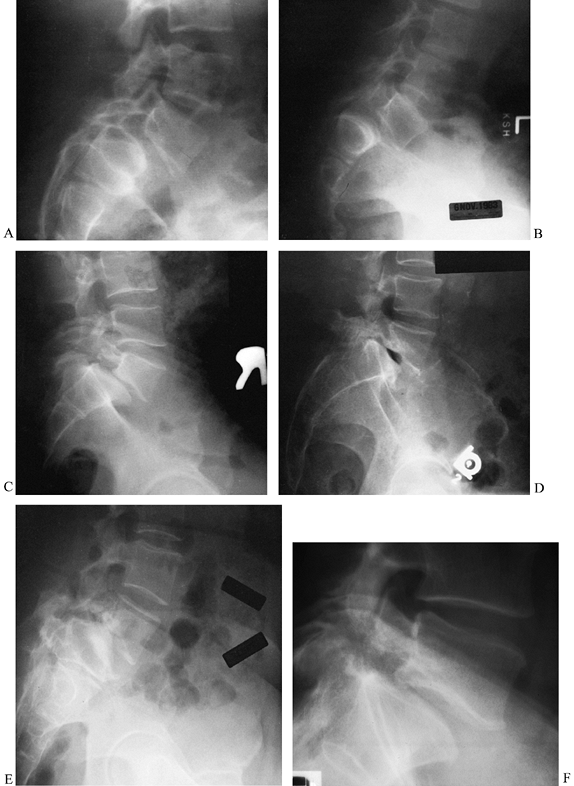

the amount of vertebral subluxation; often, they also reveal a pars

interarticularis defect if one is present (Fig. 162.4). Oblique views have also been used to highlight the Scotty-dog sign (Fig. 162.5). In young patients, flexion–extension

lying in the lateral decubitus position rather than standing (60). Plain standing radiographs are also quite useful for documenting progression of deformity (Fig. 162.6).

Figure 162.4.

Spondylolisthesis in five patients with varied combinations of slippage, slippage angle, sacral inclination, sacral rounding, and disc degeneration. A: Moderate dysplastic spondylolisthesis. No pars defect is seen, and the slippage angle is low. B: Moderate isthmic spondylolisthesis. A pars defect is seen, and the slippage angle is higher than in the previous image. C: Moderate isthmic slip with moderate disc degeneration. The slippage angle is low, but striking retrolisthesis is present at the level above (L4-5). D: Moderate isthmic slippage with severe disc degeneration and a vacuum disc. E: High-grade slip with a higher slippage angle, vertical sacrum, high lumbar index, and severe disc degeneration. F: Low-grade slip with low slippage angle and minimal disc degeneration. A pars defect is present. |